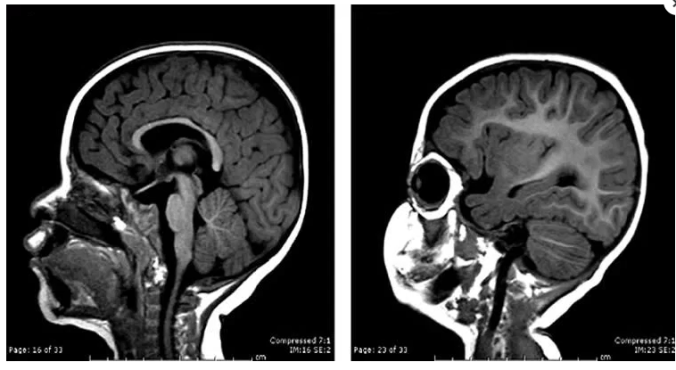

Figura 1Imagem de ressonância magnética de um encéfalo de um recém-nascido com encéfalo no tamanho esperado (esquerda) e de um com microcefalia (direita).